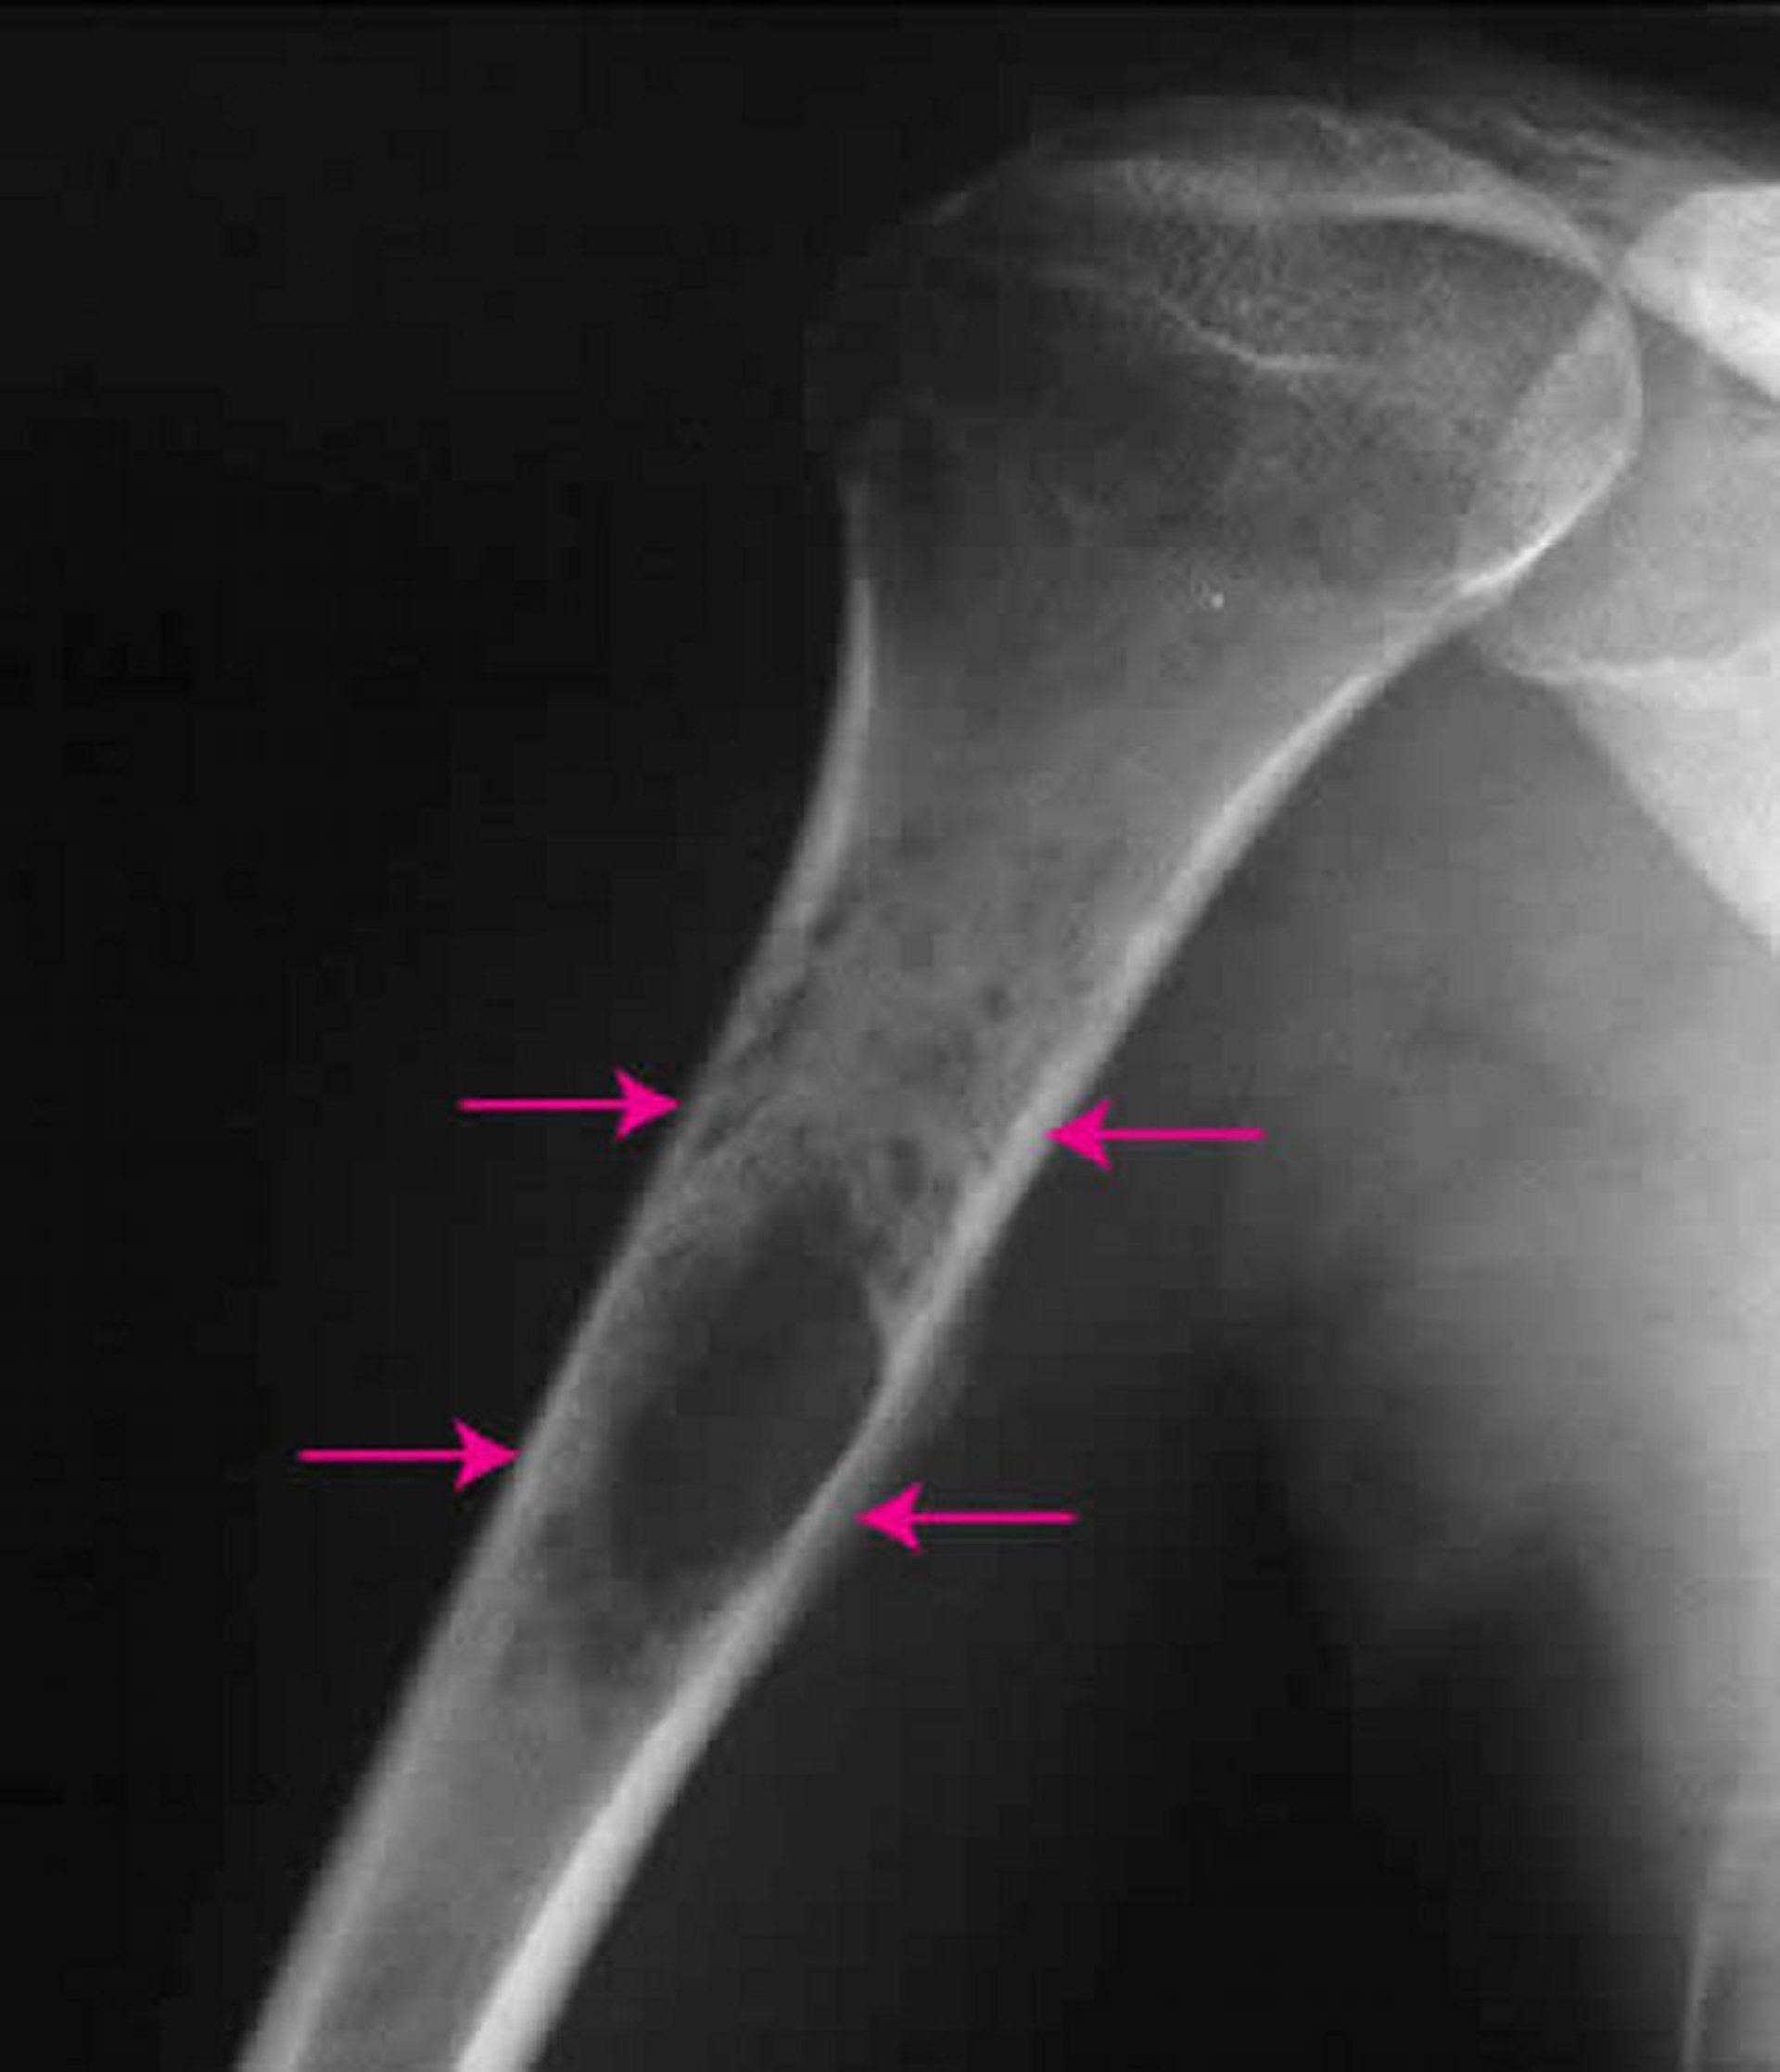

Sarcome osseux d’Ewing

Cette radiographie de l’épaule montre un sarcome d’Ewing (flèches) au niveau de l’os de l’avant-bras.

Image publiée avec l’aimable autorisation des Drs Michael J. Joyce et Hakan Ilaslan.